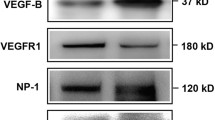

Increases in VEGF have been positively correlated with diabetic retinopathy. Therefore, we examined the impact of modulating p75NTR on VEGF expression. As shown in Fig. 3a, retinal expression of VEGF was significantly increased in diabetic vs control mice. Oral treatment with LM11A-31 led to a significant decrease in retinal VEGF expression in the diabetic mouse (Fig. 3a). Retinal vascular permeability was assessed by extravasation of BSA-conjugated AlexaFluor-488. After 6 weeks of diabetes, there was significant increase in retinal vascular permeability (~twofold) in the retinas from diabetic mice, as compared with control mouse retinas (Fig. 3b). Oral treatment with LM11A-31 significantly decreased the diabetes-induced increase in vascular permeability compared with vehicle treatment (Fig. 3b). These results support a pivotal role for upregulated proNGF/p75NTR in mediating diabetes-induced retinal inflammation and vascular permeability.

Impact of treatment with LM11A-31 on mouse retinal VEGF expression and vascular permeability. (a) Representative western blot and bar graph showing a significant increase in retinal VEGF expression in diabetic mice vs controls. This effect was abolished by treatment with LM11A-31 (n = 5–6). (b) Retinal vascular permeability was assessed by extravasation of BSA–AlexaFluor-488 after 6 weeks of streptozotocin-induced diabetes. Fluorescence was measured in retinal lysates and normalised to protein content (mg) and fluorescence intensity in serum samples from the same mouse. Diabetes induced a significant increase (~twofold) in retinal vascular permeability vs controls and this was significantly attenuated by treatment with LM11A-31 (n = 6). *p < 0.05 vs all other groups, two-way ANOVA, Cont, control mice; C+LM, control mice treated with LM11A-31; Diab, diabetic mice; D+LM, diabetic mice treated with LM11A-31